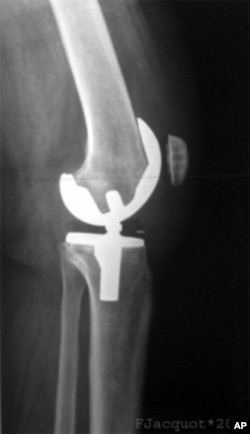

This x-ray shows shows an artificial knee joint, but now scientists are exploring regenerating damaged joints using a patient's own stem cells.

These replacement joints can be made of combinations of metal alloys, plastic and ceramic, but new research shows that it might be possible to regenerate damaged joints using a patient's own stem cells.

The disease causes cartilage-protecting joint surfaces to degrade, allowing painful bone-to-bone contact. Osteoarthritis is usually treated with pain relievers and anti-inflammatory drugs, but in severe cases, the damaged joint can be replaced with an artificial one. However, this option may not work well for the growing population of younger arthritic patients.

"The average lifespan of the metal joints is about 10 to 15 years," says Jeremy Mao at the Columbia University Medical Center. "So as you can imagine, if you are say 50, 55 or younger, the surgeons will be very hesitant to place these metal joints in your body because knowing that in 10 to 15 years, there's a chance these would fail."